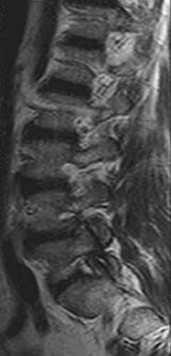

CLINICAL SITUATION FOR QUESTIONS 37 THROUGH 39

A 22-year-old woman has had right hip pain for 12 months. Her symptoms have not improved with nonsurgical treatment involving physical therapy and intra-articular injections.

The plain radiographs and MR image shown in Figures 37a through 37c indicate which condition?

- Cam-type femoroacetabular impingement with an acetabular labral tear

The radiographic studies reveal both acetabular dysplasia and cam-type femoroacetabular impingement. The MR image shows an acetabular labral tear. Structural abnormalities of the hip, including femoroacetabular impingement, have commonly been identified in association with labral tears. Disruption of the ligamentum teres is not associated with impingement conditions in the absence of trauma.

The patient has acetabular dysplasia with a decreased lateral center-edge angle and also has visible cam-type femoroacetabular impingement. The common pathway for joint degeneration in hips with cam-type femoral head anatomy includes the development of cartilage damage in the anterior or superolateral aspects of the acetabular cartilage. Paralabral cysts may be seen more commonly in association with acetabular dysplasia, although the patient’s radiographs did not demonstrate substantial cystic changes. Osteochondral loose bodies and ligamentum teres ruptures can be seen at arthroscopy in a small number of cases.

There are several proposed roles of the acetabular labrum. It can increase the depth of the acetabular socket by as much as 21% to 28%. Roles of the acetabular labrum include joint lubrication, shock absorption, and pressure distribution. Recent studies assessing the effects of loading on joint stability for both normal and dysplastic hips did not demonstrate a substantial role of the labrum in differences in loading. Although joint stability might be improved following surgical repair, acetabular dysplasia is not likely to be resolved with acetabular labral repair alone.